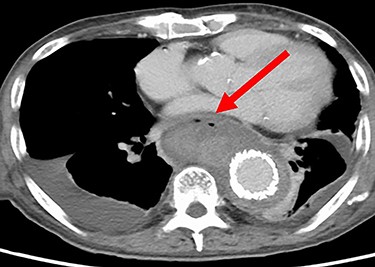

The patient was an 81-year-old man with a history of maintenance dialysis due to diabetic nephropathy, right hemicolectomy due to transverse colon cancer, coronary artery bypass grafting and abdominal aorta-femoral-popliteal bypass surgery due to peripheral arterial disease. The patient complained of anorexia for the last 1 month, and a screening computed tomography (CT) scan revealed a ruptured descending aorta (Fig. 1). He was transferred to our hospital for surgical management. At the time of admission, his vital signs were stable, but blood tests indicated a systemic infection, given that his leukocyte count was 14 510/μl and C-reactive protein was 27.92 mg/dl.

CT at the time of admission shows irregular shape of the aneurysm.